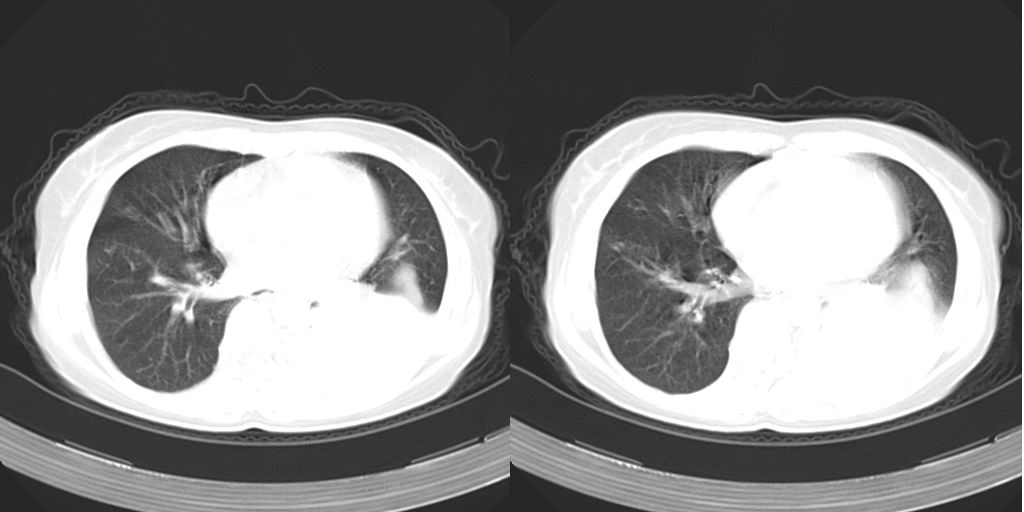

以下是引用dyqct在2007-1-23 15:01:00的发言:[br]左肺下叶实变、略萎陷,近肺门下部密度不均。上腔静脉后及隆突前见肿大淋巴结。余未见异常。[br]考虑:1、左肺下叶中心型肺癌伴肺不张、纵隔淋巴结转移;[br] 2、建议增强扫描并做任意平面重建确定肿块范围及支气管受累情况。

以下是引用同在2007-1-23 19:59:00的发言:[br]左肺下叶中央型肺癌伴肺不张及纵隔淋巴结转移.